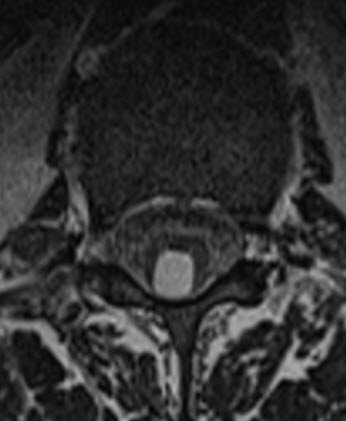

Axial T1 weighted MRI showing the cystic lesion adherent to the dura.

Coronal T2 weighted MRI showing the cystic lesion inside the conus medullaris.